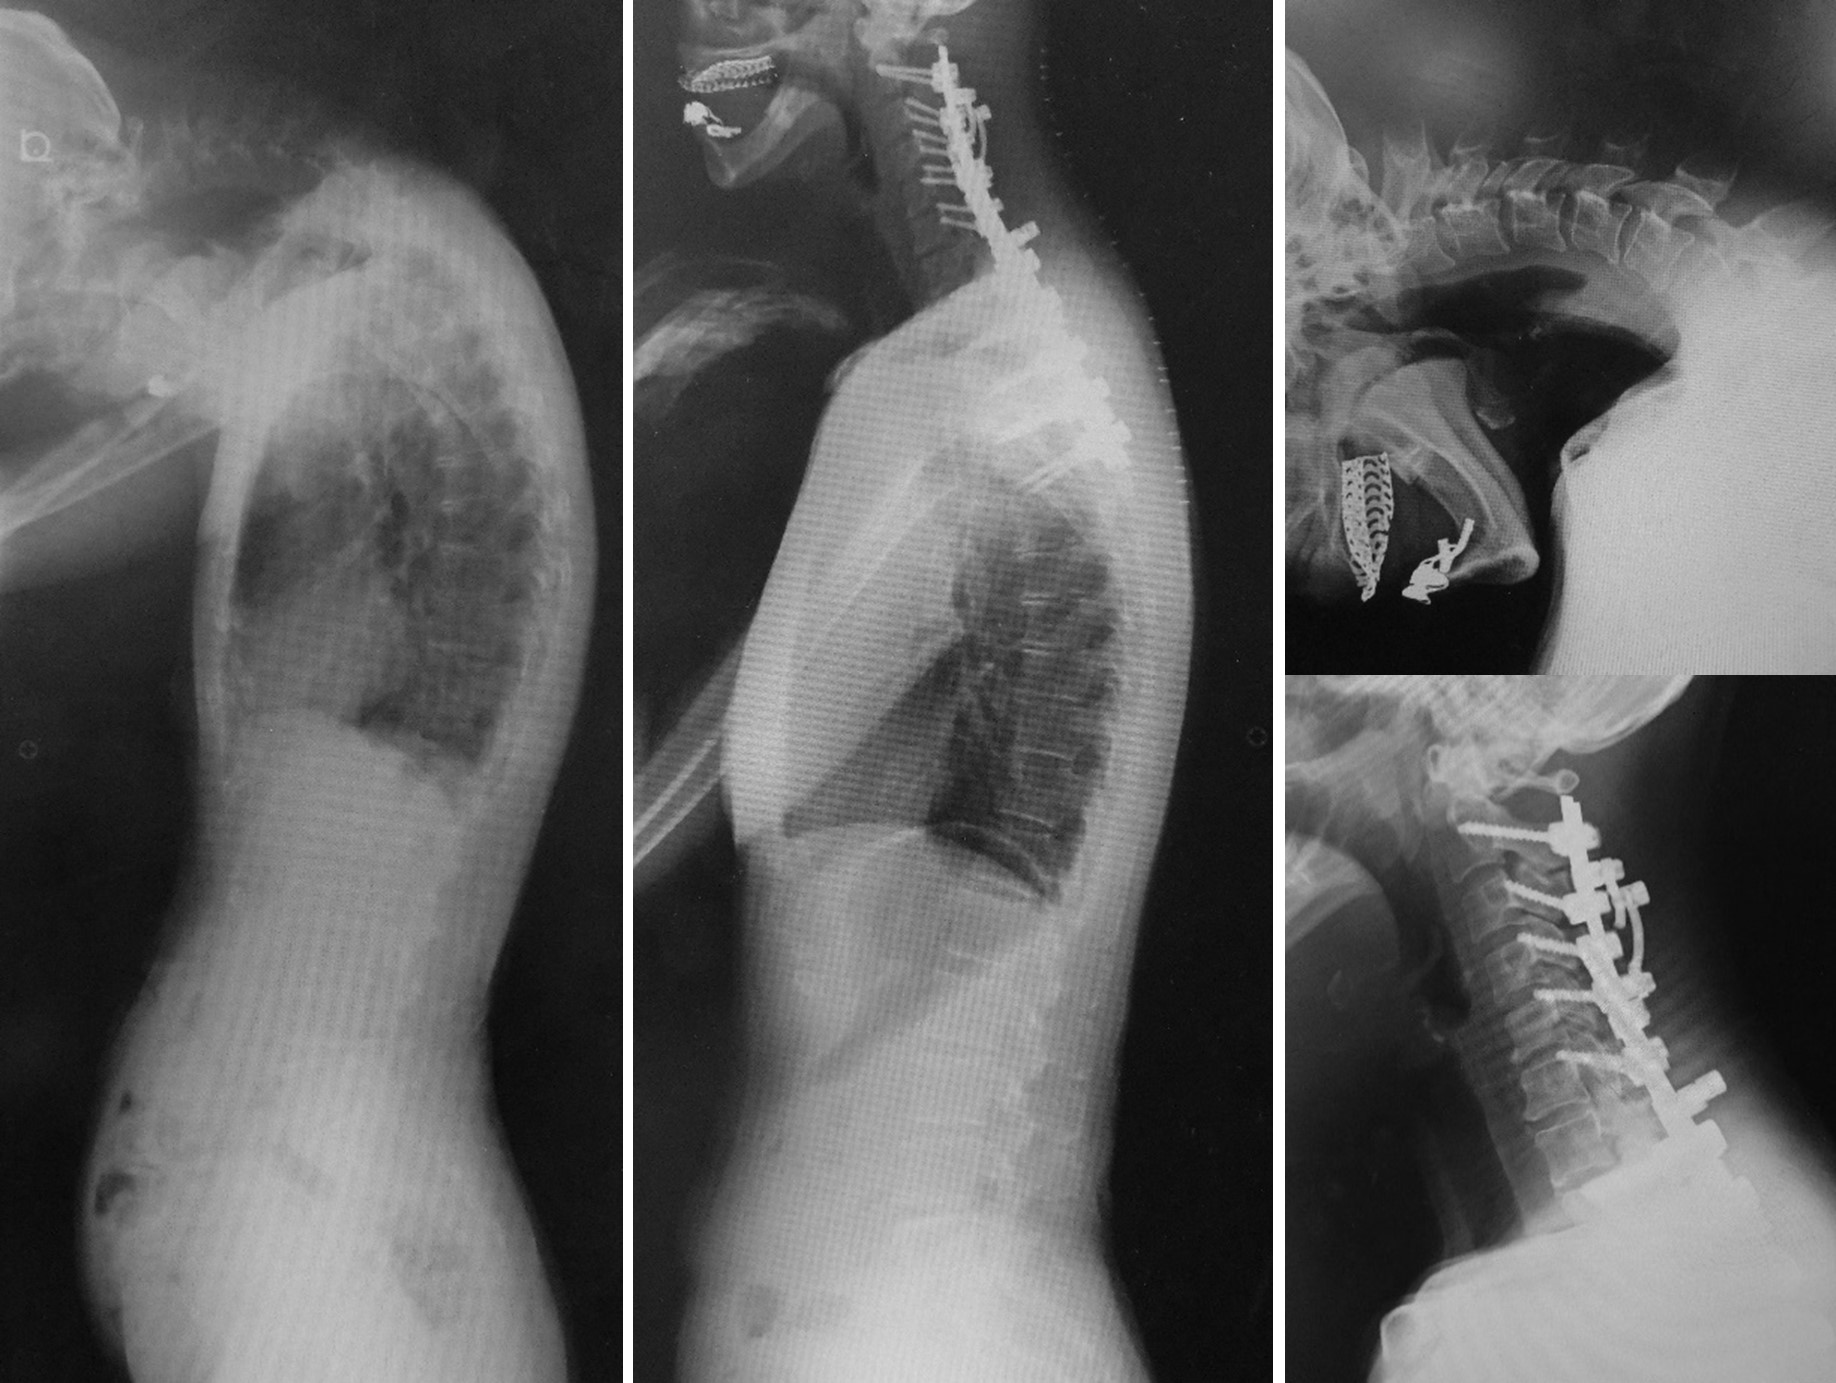

図 首下がり(くびさがり)症候群に対する頚椎後方固定術

(左)ご高齢の方に多く発症する、頭が下を向いてしまって持ち上がらない首下がり病という疾患があります。前方が見れないため、日常生活に不便を生じたり、嚥下障害で食事が十分にとれないこともあります。

(まん中、右)本症例では、金属製のスクリューを用いて頚椎が大きく矯正固定され、前方が見れるようになりました。